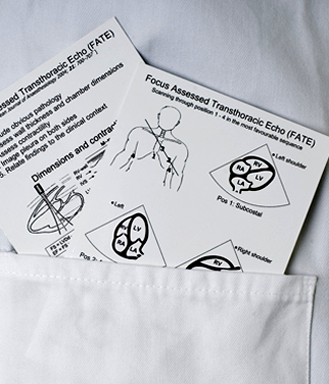

The primary clinical application of ultrasound today is as a diagnostic tool and as a means to display anatomical structures, for which frequencies between 1 and 20 MHz are most commonly used